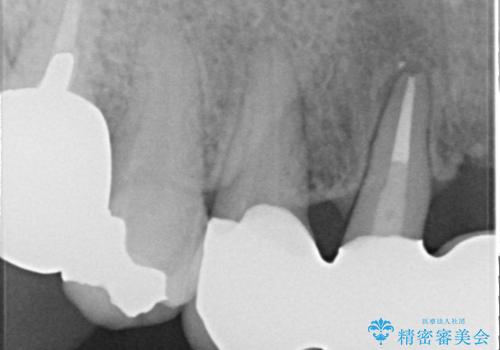

レントゲンを撮影すると保存が難しい歯がありました。

①保存不可の歯の抜歯・根管治療

②矯正治療

③セラミックの装着

という流れで行いました。

1年程度の治療期間が必要となりましたが、仕上がりには患者様に満足していただけました。